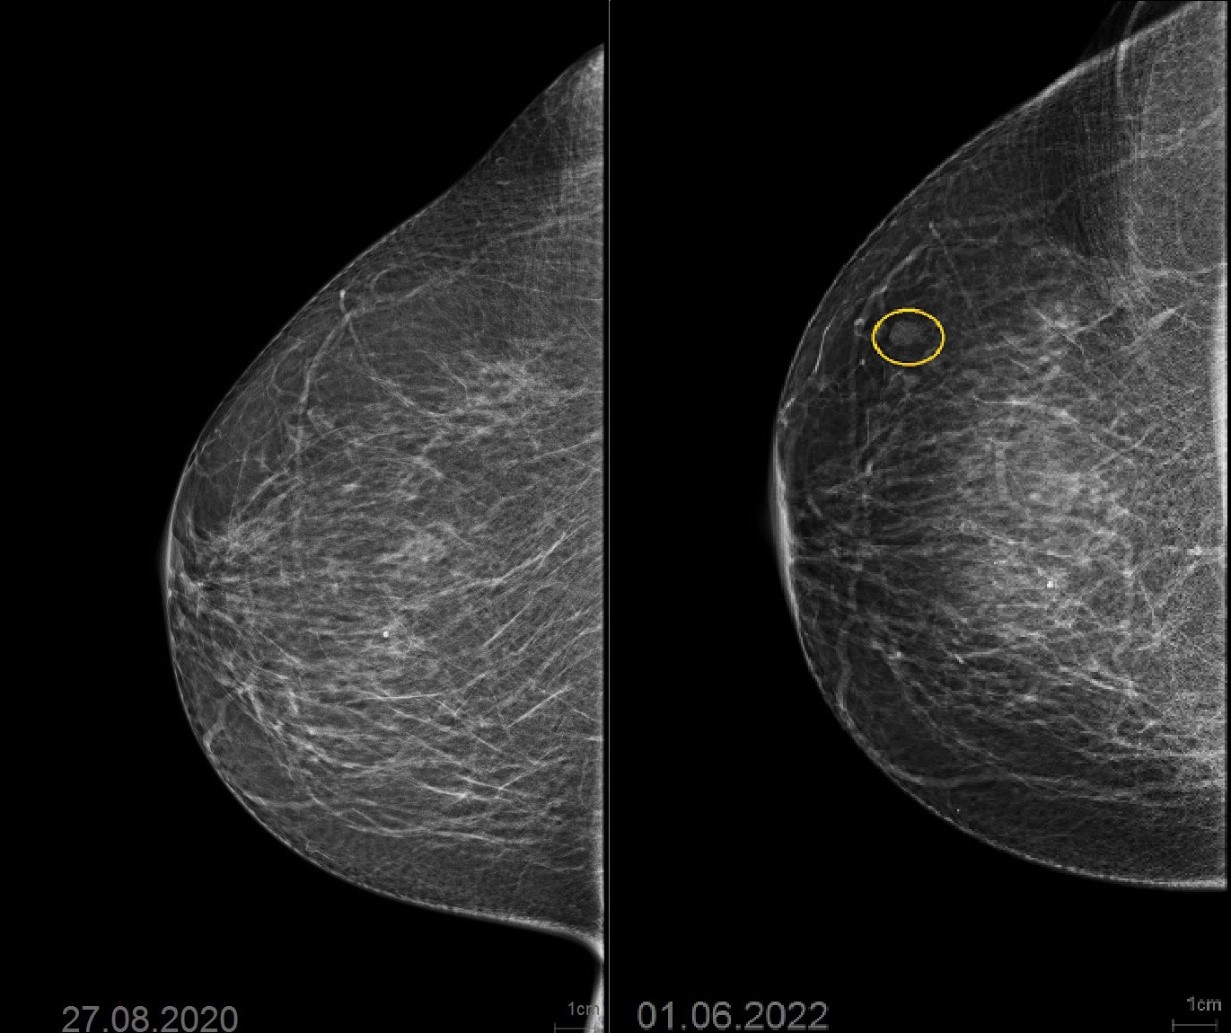

Аномалии молочной железы: медицинские примеры и визуализация

Раздел: Мудрость в деталях